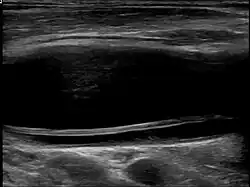

Diagnostic method | Ultrasound, MRI, MRA, CTA |

Carotid artery dissection can occur spontaneously or be triggered by trauma, including minor injuries, certain medical conditions, or activities that involve neck movement. It is a leading cause of stroke in young and middle-aged adults. The condition is typically diagnosed through imaging studies, such as ultrasound, magnetic resonance imaging (MRI), magnetic resonance angiography (MRA), or computed tomography angiography (CTA), which help visualize the blood vessels and detect abnormalities.